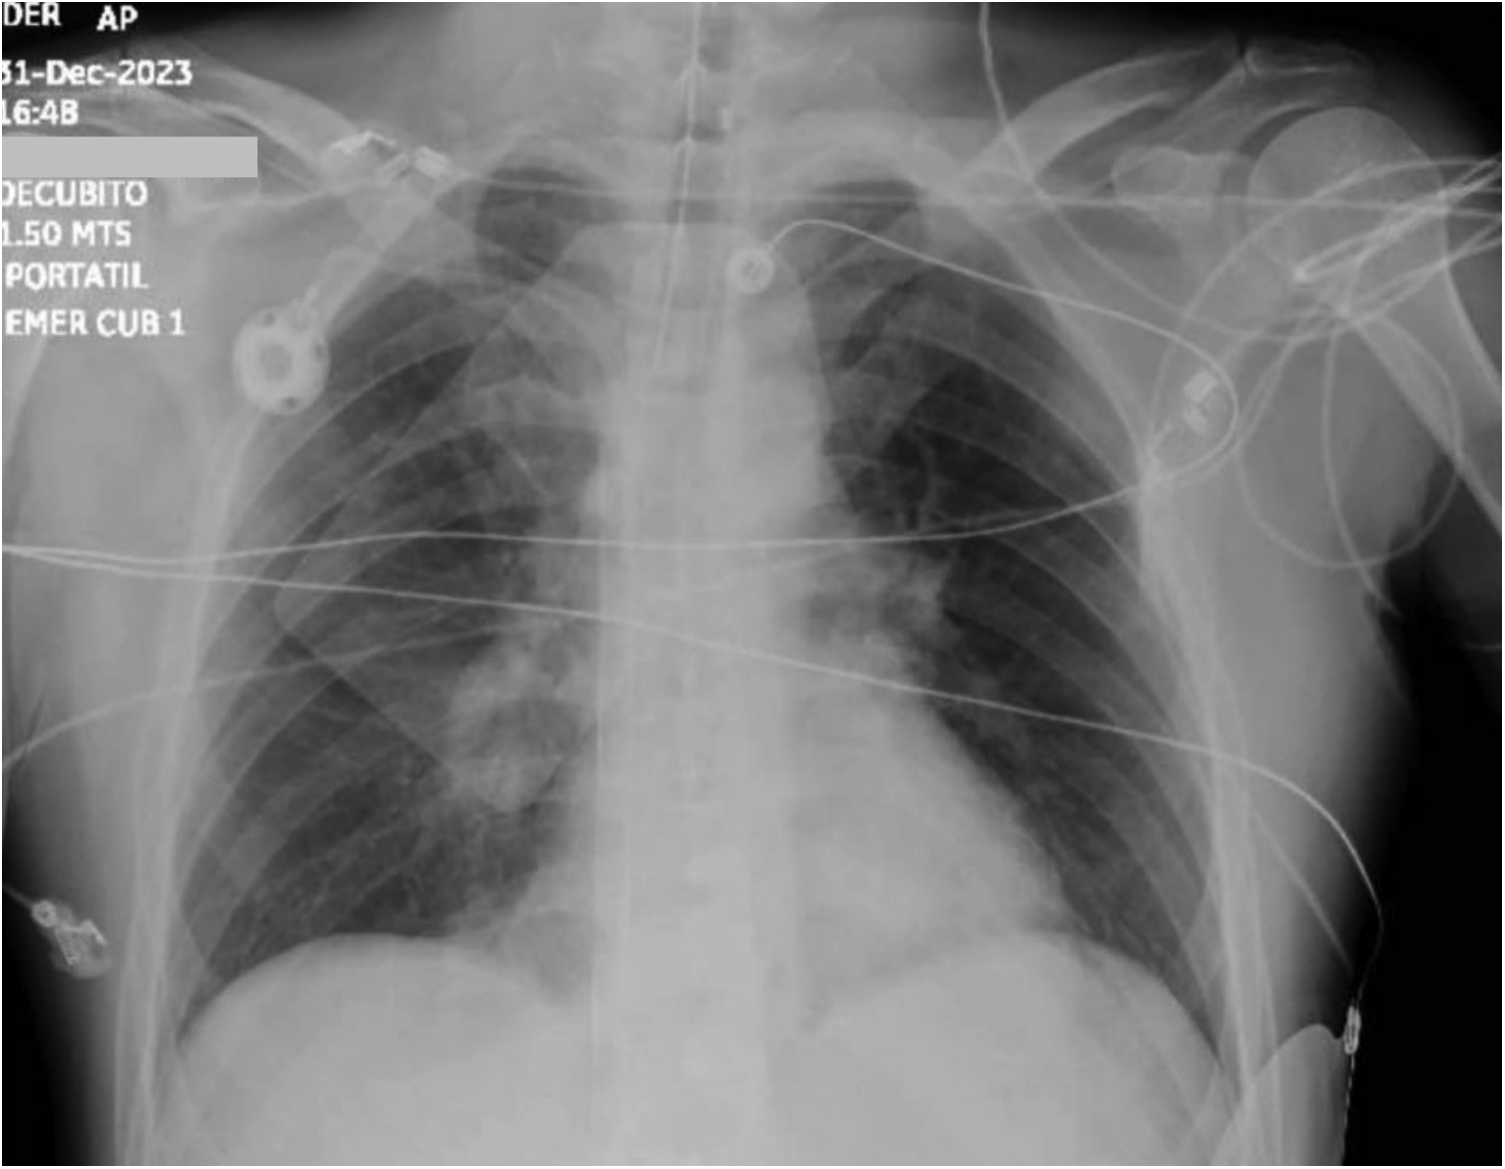

On December 31, a 61-year-old male presented to the emergency room with a 30-min history of sudden-onset resting dyspnea associated with diaphoresis, cyanosis, and weakness. His past medical history included a recent diagnosis of colon cancer treated with colectomy and oxaliplatin-based chemotherapy. On arrival, the patient's temperature was 35.6°C. He was clinically unstable, with hypotension (52/42 mmHg), bradycardia (41 bpm), tachypnea (26 rpm), and oxygen desaturation (86%). On physical examination, chest auscultation revealed diminished cardiac sounds and bibasilar crackles, along with decreased respiratory sounds. Peripheral pulses were reduced, and the capillary refill time was 4 s. Ten minutes after admission, the patient underwent sudden cardiac arrest. Therefore, we initiated mechanical cardiopulmonary resuscitation (CPR) using a Lund University Cardiopulmonary Assist System (LUCAS) device with simultaneous activation of the shock team. We carried out eight cycles while concurrently administering 5 mg of epinephrine and 80 mEq of sodium bicarbonate. The patient returned to spontaneous circulation after 21 min of mechanical CPR. Initial venous blood gas analysis revealed pH <6.8, PO2 32 mmHg, PCO2 100 mmHg, and lactic acid >15 mmol/L. Initial chest x-ray during “code blue” activation showed right pulmonary artery amputation and bilateral Westermark sign (Figure 1). Subsequently, a second cardiac arrest occurred, requiring LUCAS-assisted CPR and five defibrillation events. The shock team concluded that conventional CPR had been unsuccessful and decided to initiate VA-ECMO while continuing chest compressions (extracorporeal CPR). Using ultrasound guidance, a 5 French micropuncture kit was employed to access the common femoral artery and vein. Compressions were paused for up to 60 s during vessel needling, with the team leader overseeing these intervals. A 0.035-inch venous guidewire was confirmed to be in the inferior vena cava, and the arterial guidewire was then advanced. We used the arterial and venous introducer cannulas for vessel dilation instead of serial dilators, as this method was safer and reduced cannulation time. A femoral artery distal perfusion cannula was not required for the initial deployment. We also started unfractionated heparin, aiming for an activated thromboplastin time between 180 and 220 s. Laboratory results revealed a D-Dimer (DD) 38,892 mcg/ml (0–500 mcg/ml), high sensitivity troponin (hs-c-TnI) 7 ng/L (0–35 ng/L), and B-type natriuretic peptide (BNP) 106 pg/ml (<100 pg/ml). Cardiac tracking with point-of-care ultrasound showed right atrial and ventricular dilation with interventricular septum deviation and left ventricular collapse. An ECG showed sinus rhythm, flattened T waves in the right precordial (V1) and inferior (II, III and aVF) leads, and ST depression from V4 to V6. We established a high clinical suspicion of high-risk PE associated with recurrent cardiac arrest and SCAI E CS based on risk factors, clinical presentation, imaging findings, and biomarkers. CT angiography was not performed due to the patient's unstable condition.

Figure 1

Chest x-ray shows right pulmonary artery amputation and bilateral Westermark sign.